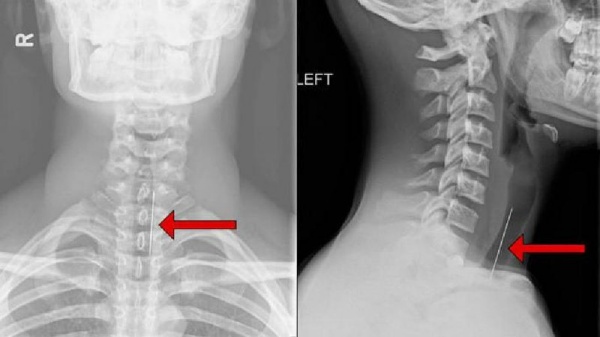

Hình ảnh Xquang cột sống cổ

Hình ảnh Xquang cột sống cổ ít có giá trị trong chẩn đoán xác định bệnh lý thoát vị đĩa đệm cột sống cổ. Tuy nhiên hình ảnh Xquang cột sống cổ có thể gián tiếp gợi ý đến thoát vị đĩa đệm cột sống cổ như cột sống mất đường cong sinh lý, lệch vẹo cột sống, trượt đốt sống ra trước, hẹp khe gian đốt sống… Có thể thấy hình ảnh thoát vị Schmorl biểu hiện là những nốt xơ hóa và lõm vào thân đốt sống. Hình ảnh Xquang chếch 3/4 có thể đánh giá lỗ liên hợp.

Hình ảnh mất đường cong sinh lý

Chúng tôi tiến hành chụp Xquang cột sống cổ thẳng – nghiêng tư thế tĩnh và tư thế động (cúi tối đa, ngửa tối đa) cho tất cả người bệnh thuộc nhóm nghiên cứu. Chúng tôi nhận thấy rằng có 11/30 người bệnh cho hình ảnh mất đường cong sinh lý cột sống cổ chiếm tỷ lệ 36,7% (bảng 1).

Khi nghiên cứu người ta thấy do sự thoái hóa của cột sống cổ, sự co cơ để đối kháng lại triệu chứng đau là nguyên nhân chính gây biến đổi đường cong sinh lý cột sống. Quá trình thoái hóa lâu ngày làm giảm tầm vận động của cột sống gây gù, lệch vẹo cột sống cổ. Những người bệnh này khi phẫu thuật ngoài việc giải phóng chèn ép tủy, rễ thần kinh thì cần cố gắng thiết lập lại giải phẫu sinh lý của cột sống cổ.

Nguyễn Quốc Dũng [1] nghiên cứu 52 người bệnh thoát vị đĩa đệm cột sống cổ tai bệnh viện Việt Đức cho thấy tỷ lệ người bệnh mất đường cong sinh lý cột sống cổ là 84,62%. Hoàng Văn Chiến [2] nghiên cứu tỷ lệ này là 96%. Nguyễn Văn Thạch, Hoàng Gia Du [3] là 26,7%.